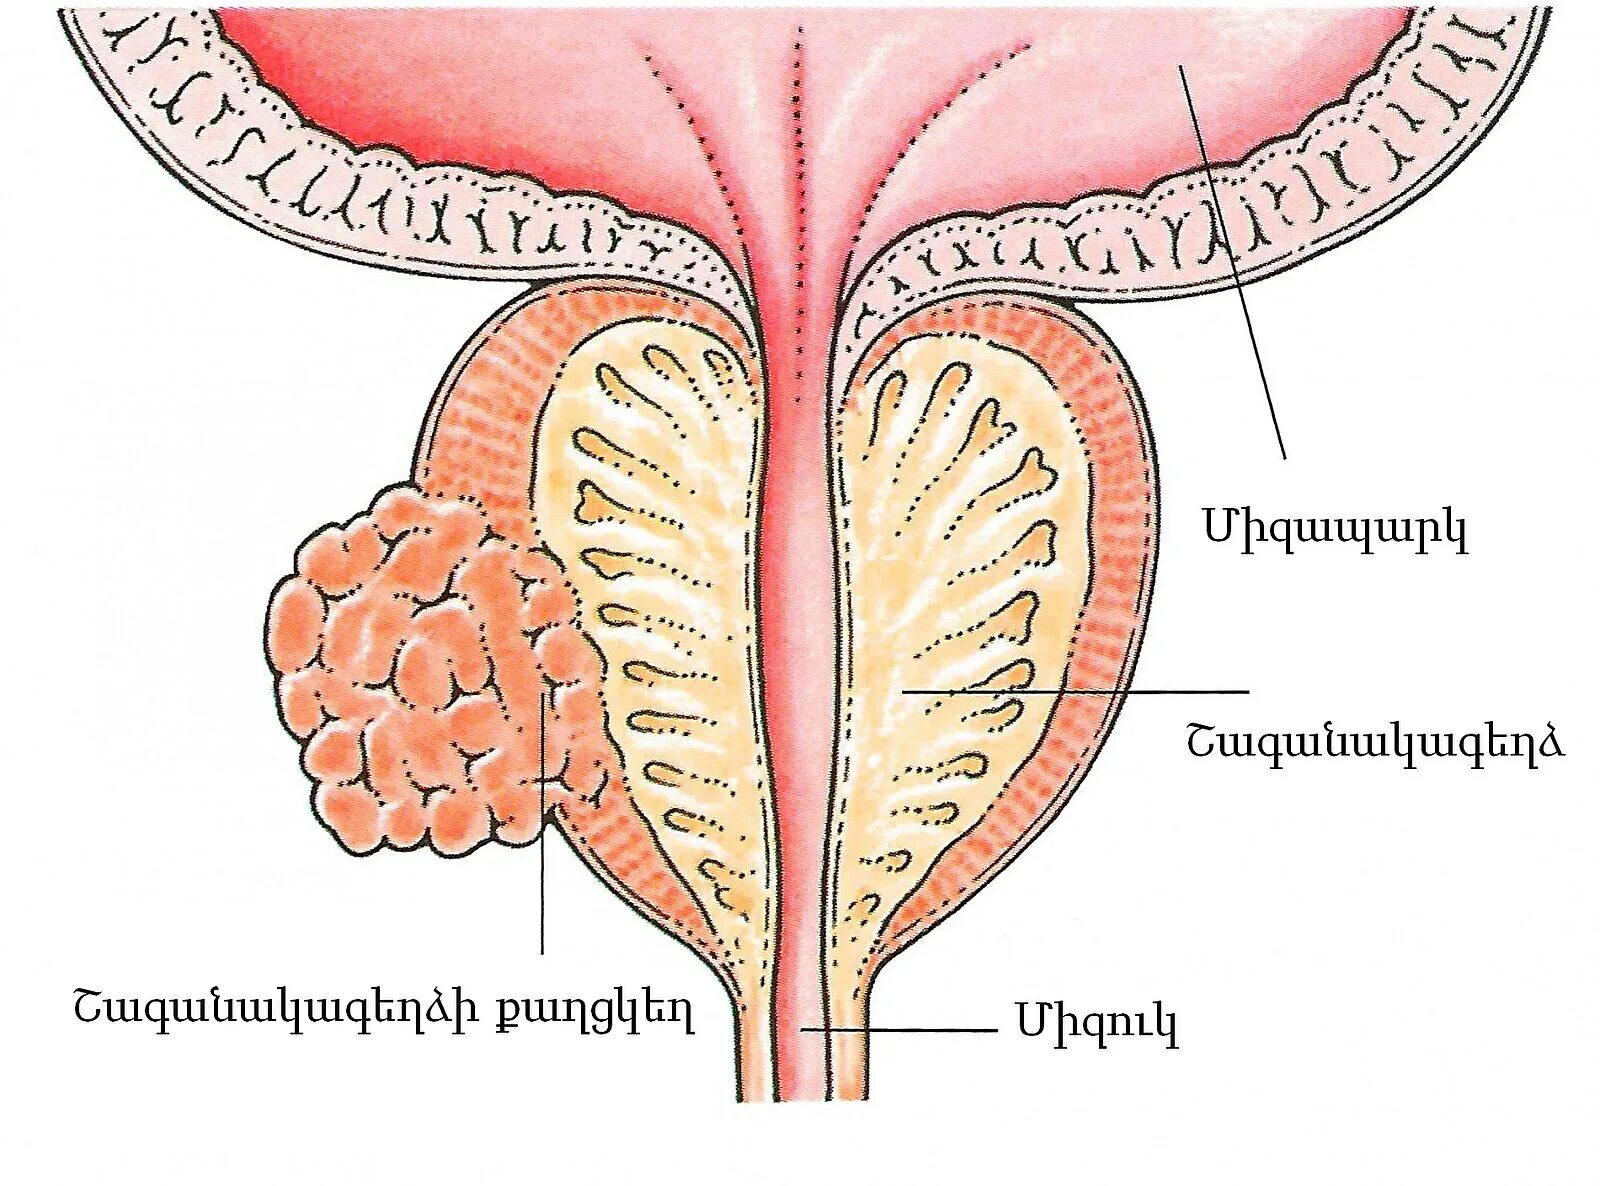

Предстательная железа в пожилом возрасте. Простатит 3 степени 2 класс. Метастазы простата рисунок Новообразование предстательной железы. Хирургическая капсула простаты. Tumor предстательной железы. Объемное образование в простате

Новообразование предстательной железы. Хирургическая капсула простаты. Tumor предстательной железы. Объемное образование в простате Онко предстательной железы. Онкология простаты симптомы. Злокачественная опухоль предстательной железы. Карцинома предстательной железы

Злокачественное новообразование предстательной железы. Карцинома предстательной железы. Susp BL предстательной железы что это. Tumor предстательной железы Предстательная железа, Prostata. Карцинома предстательной железы. Простата и предстательная железа. Предстательная железа 3д

Предстательная железа, Prostata. Карцинома предстательной железы. Простата и предстательная железа. Предстательная железа 3д Ракпристательныйжелезылечение. Лекарство онкология предстательной железы. Лучевая терапия опухоли предстательной железы

Образование в предстательной. Образование в предстательной железе. Опухоль простаты у мужчин Аденома предстательной железы. Злокачественная аденома предстательной железы. Аденомопредстательная железа

Аденома предстательной железы. Злокачественная аденома предстательной железы. Аденомопредстательная железа Бульбоуретральные железы гистология. Бульбоуретральная железа гистология. Куперовы железы гистология. Бульбоуретральная железа препарат гистология

Анатомия аденомы предстательной железы. Эктопия предстательной железы. Злокачественная опухоль предстательной железы. Злокачественная аденома предстательной железы

Анатомия аденомы предстательной железы. Эктопия предстательной железы. Злокачественная опухоль предстательной железы. Злокачественная аденома предстательной железы Карцинома 4 степени предстательной железы. Онкология предстательной железы. Опухоль предстательной железы стадии